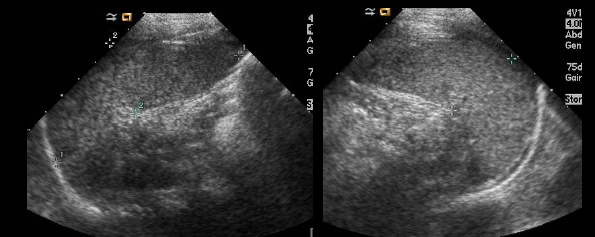

which plane are each of these spleens in? how can you tell?

lt long, rt trans

look for the hilum.